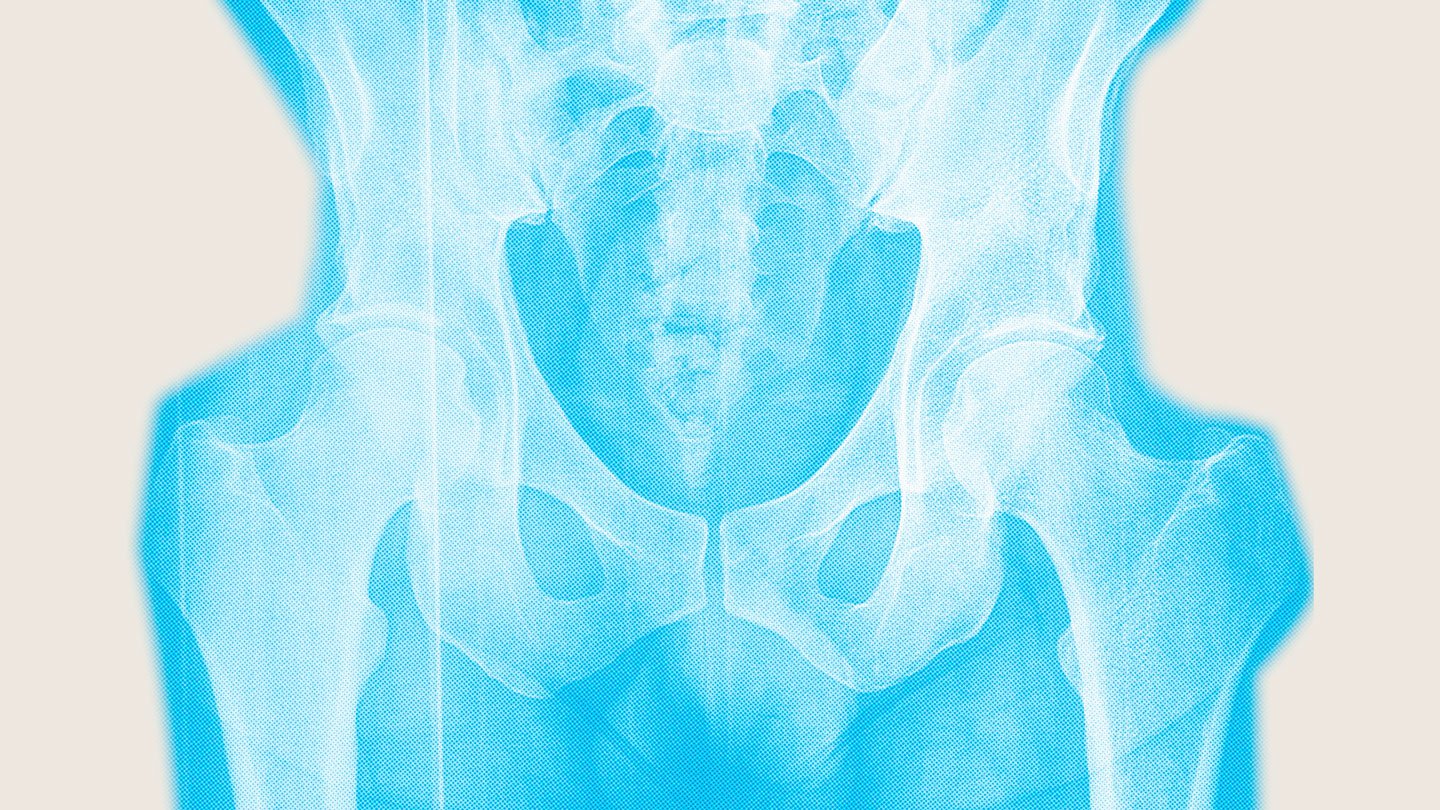

Bones weakened by osteoporosis are more likely to fracture, which can be debilitating and even deadly. Hip fractures are especially devastating. Around 20 percent of people die within one year of having a hip fracture. Only 40 to 60 percent of survivors are likely to regain their pre-fracture mobility. Lingering physical limitations degrade quality of life.